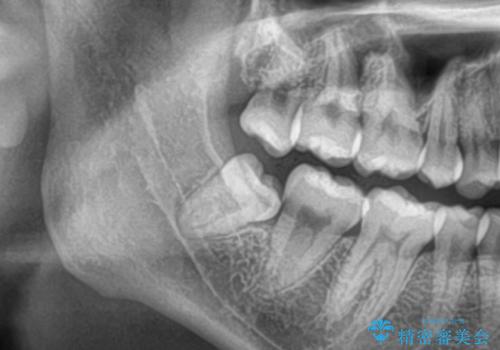

- 親知らずのところが痛く抜きたいとの事で来院。

レントゲン CTを撮影して安全な事を確認して抜歯を行いました。